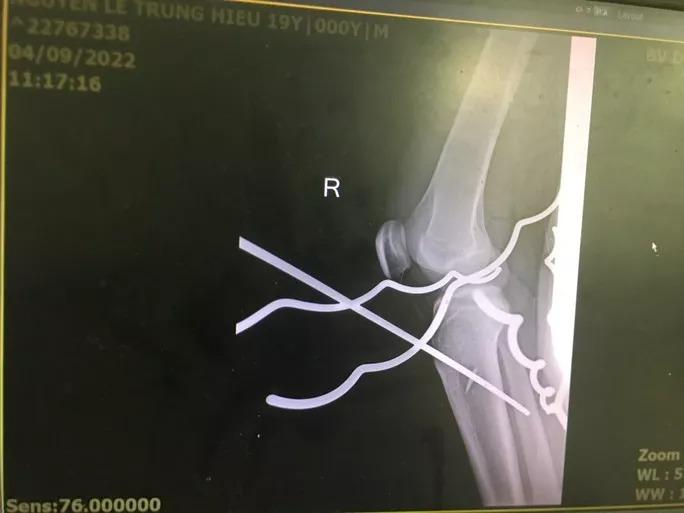

Hình ảnh chụp phim cho thấy 5 thanh sắt đâm xuyên qua chân nam thanh niên